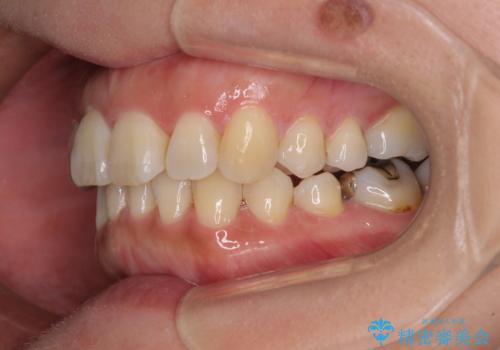

軽度な歯列不正 インビザライン・ライトによる矯正治療

- 上下前歯の叢生を気にして来院された患者様です。

費用を抑え、期間もあまりかけずに治療をしたいとのことで、インビザライン・ライトを用いて矯正治療を行うこととしました。

インビザライン・ライトは、製作できるアライナーの枚数に制限があるため、移動可能な量に限りがあります。

一方で、半年から1年程度で治療を終えることができるため、軽度の歯列不正の患者様には大変お勧めです。